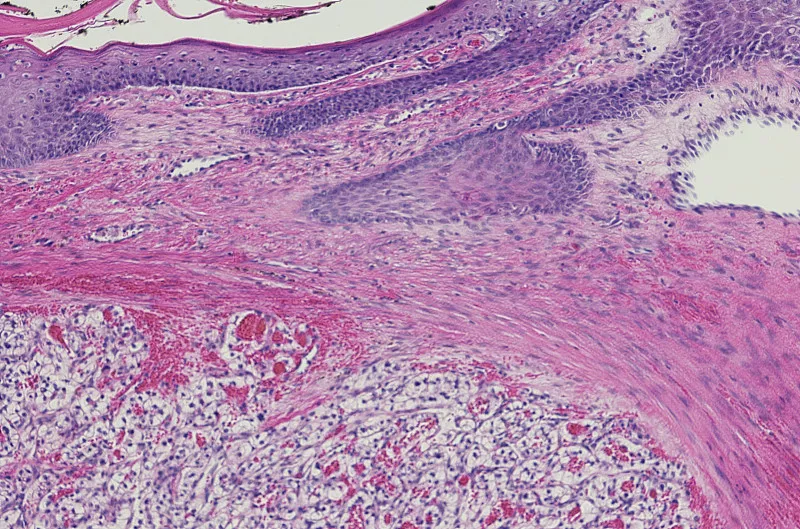

【肾癌|小心肾癌易误诊】一般来说 , 成人肾肿瘤有三种类型:80%的肾癌发生在肾实质;肾盂肾癌占20%;胚胎肾癌在成年人中很少见 。 1-3岁儿童的肾癌主要是肾胚胎瘤 , 5岁以上儿童罕见 。 当出现无痛、间歇性血尿、腹部或肾脏肿块和腰痛时 , 应使用X射线血管造影和B超 。